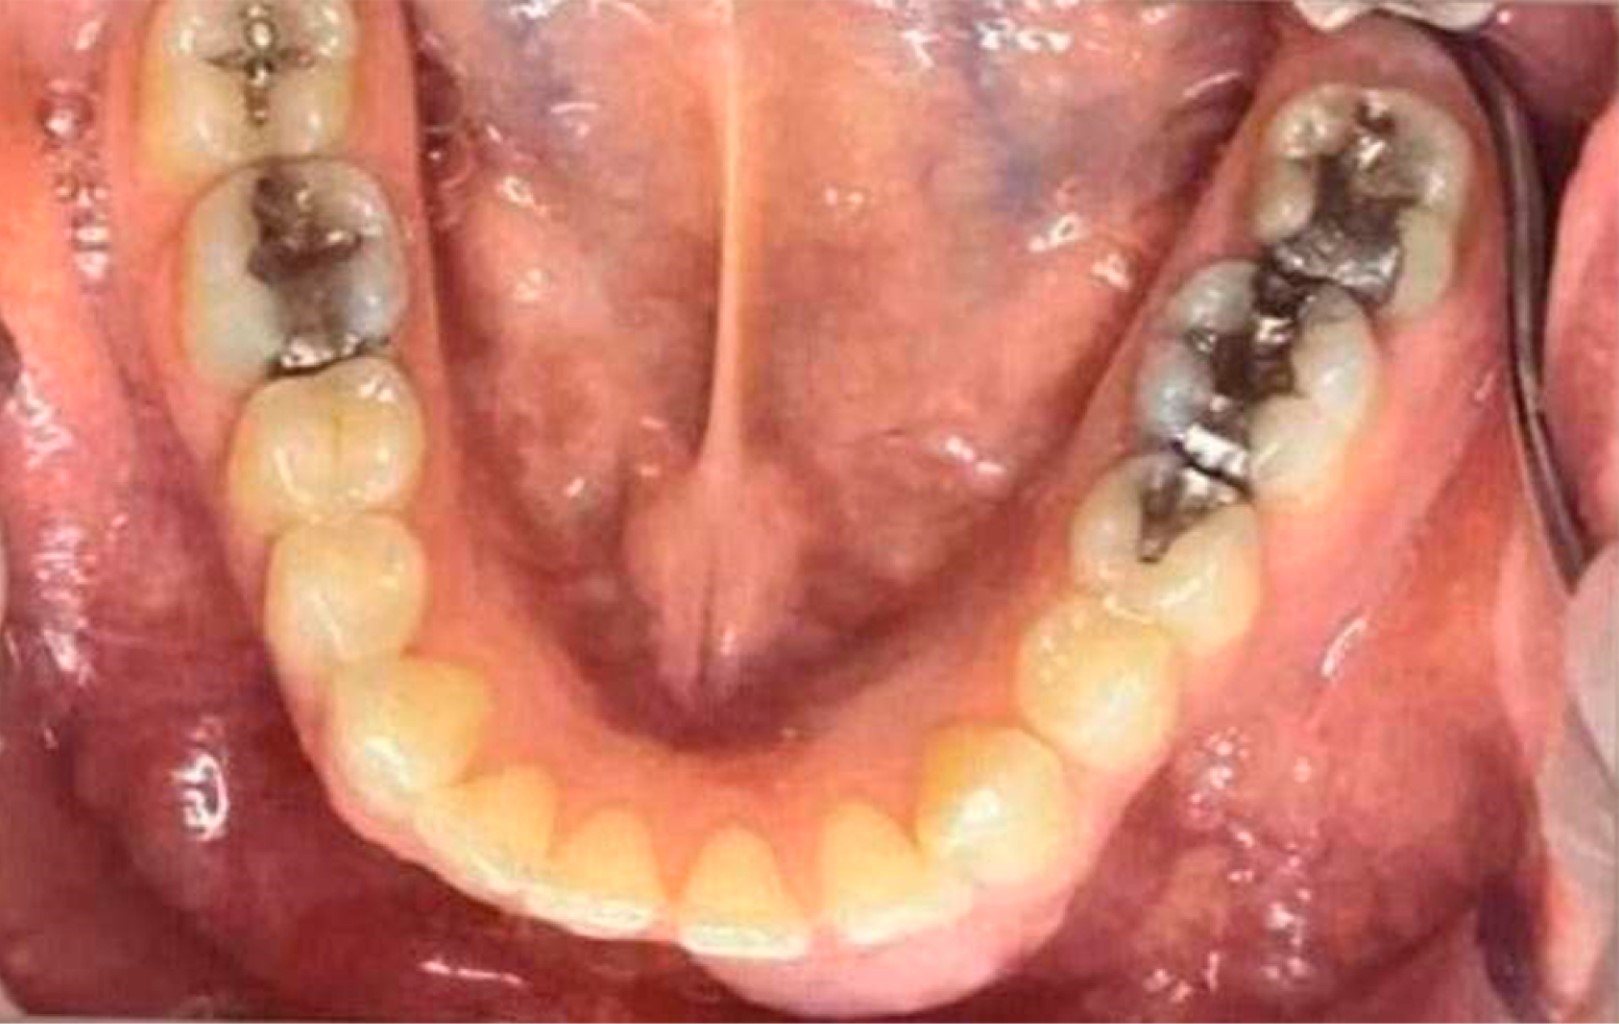

Mujer de 47 años, leucodermia, acude a la consulta de cirugía y traumatología bucomaxilofacial del Grupo Leforte refiriendo aumento de volumen en la región anterior de la mandíbula desde hace seis meses, con empeoramiento progresivo y desplazamiento de dientes. El examen físico intraoral reveló un abultamiento de las corticales óseas bucal y lingual, así como un ligero diastema entre los dientes 31, 32 y 41 (Figura 1).